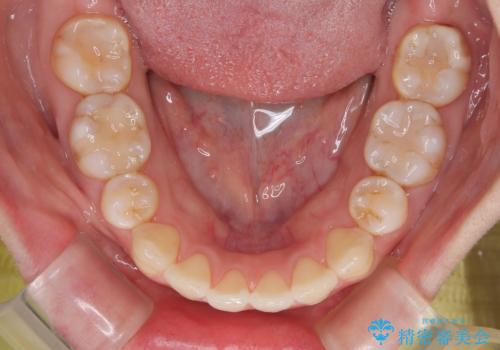

- 上下前歯の後戻りを気にして来院された患者様です。

インビザラインでの治療を希望されていて、デコボコの程度が中等度であり、安価なパッケージにて対応可能と判断されたため、インビザライン・モデレートを用いて矯正治療を行うこととしました。

インビザライン・モデレートは、製作できるアライナーの枚数に制限があるため、移動可能な量に限りがあるものの、インビザライン・ライトよりも枚数が多いため、幅広い症例に対応可能です。